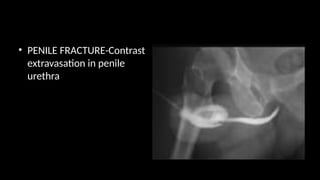

• PENILE FRACTURE-Contrast

extravasation in penile

urethra